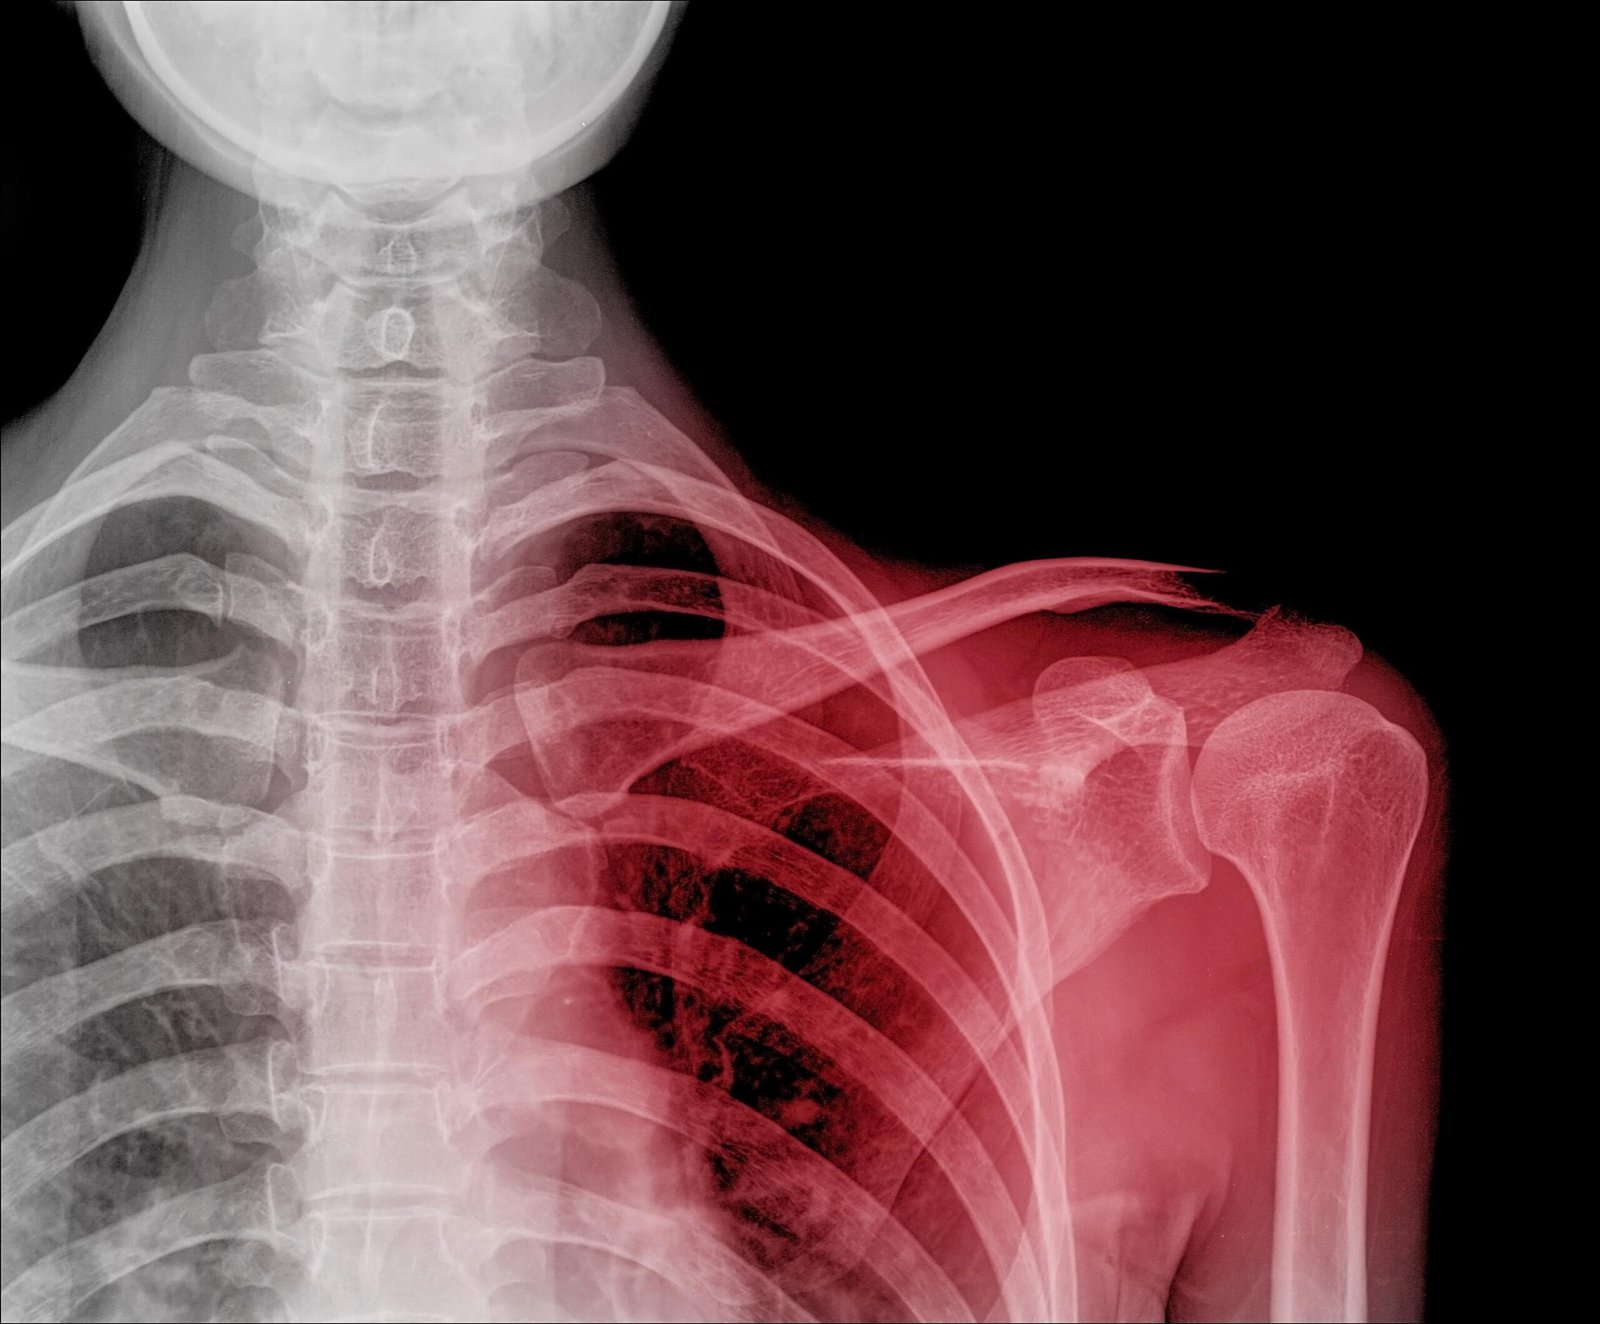

A dislocation is a displacement of one or more bones at a joint. Common joints which dislocate are shoulder, elbow, thumb finger and joint.

C) Signs:

1) Deformity of the limb. E.g. Shoulder dislocation-abduction deformity

5) In case of shoulder dislocation patients support the injured hand by the

unaffected hand.